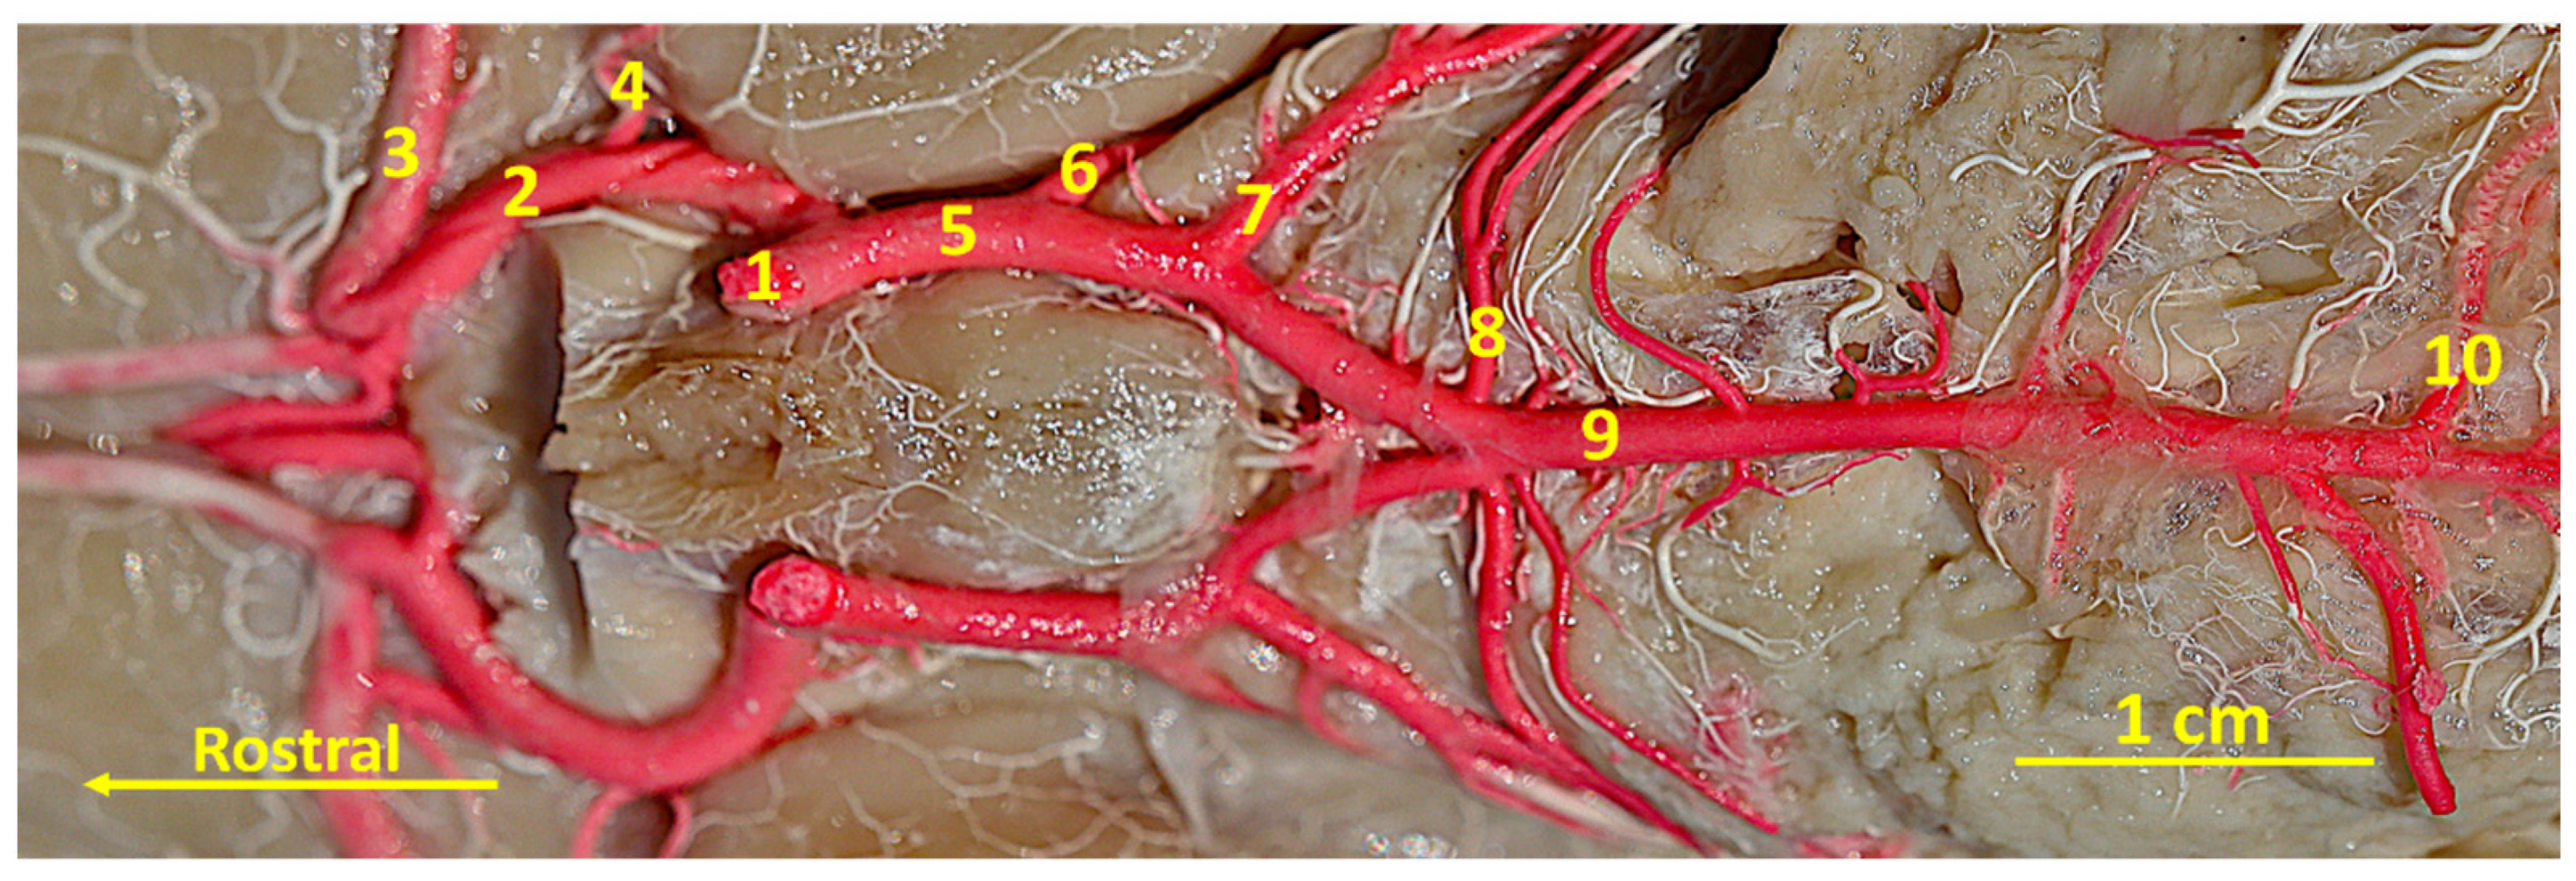

The Arterial Circle of the Brain in the Bawean Deer (Axis kuhlii)

3. Results